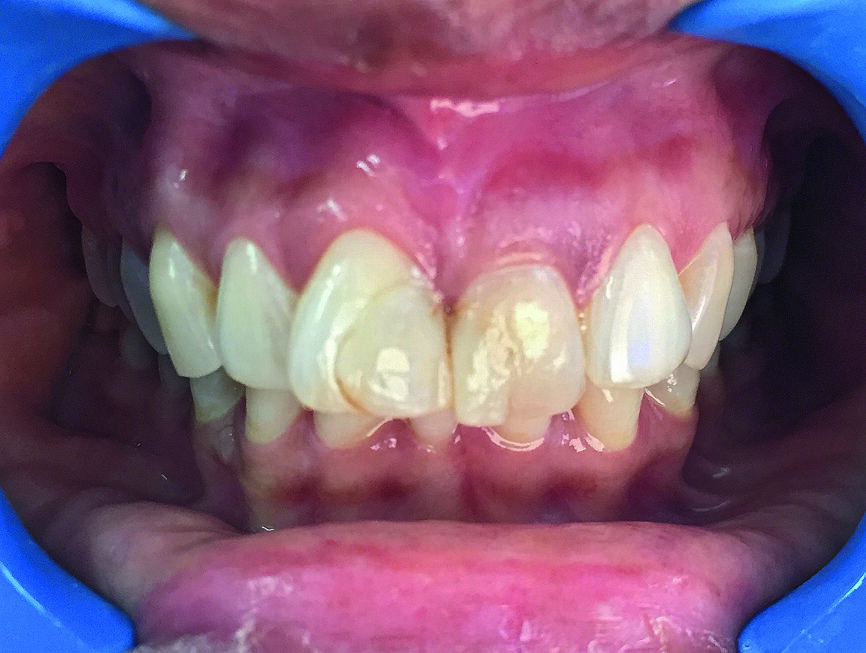

La patiente, âgée de 36 ans, nous a consulté pour un contrôle dentaire en raison d’une douleur dans la région des dents antérieures supérieures gauches. À ses dires, la douleur commençait subitement et s’aggravait lors de la mastication. L’examen clinique de l’incisive centrale supérieure gauche (dent 21) a révélé une inflammation, une douleur à la percussion et une fracture de la dent au niveau de la limite cervicale. La dent avait fait l’objet d’un traitement endodontique trois ans plus tôt et n’avait jamais été restaurée auparavant. Une radiographie a montré une couronne fracturée touchée par une résorption radiculaire mineure ainsi qu’une infection périapicale (Figs. 1a–c). L’examen radiographique comme l’examen clinique ont également confirmé la présence d’une largeur et d’une hauteur d’os suffisantes. Le pronostic très défavorable d’un retraitement endodontique a été expliqué à la patiente et elle a opté pour un traitement plus radical. La décision d’extraire la dent et de la remplacer immédiatement par un implant monobloc en zircone a donc été prise.

Fig. 1a : Photographie clinique préopératoire de la dent 21.